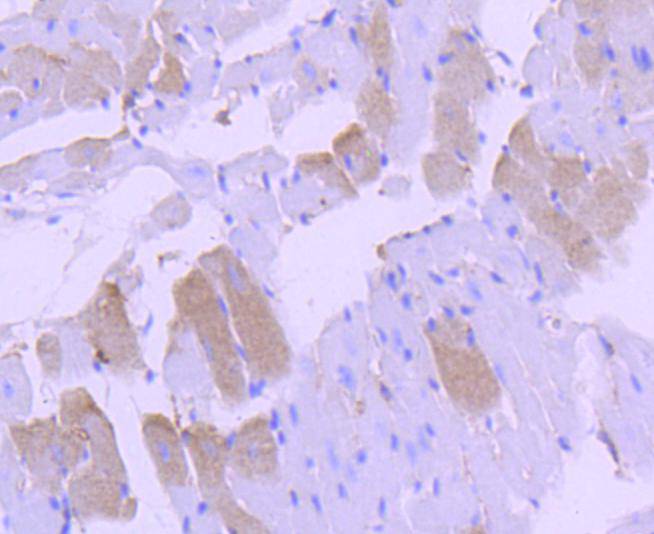

Immunohistochemical analysis of paraffin-embedded mouse heart tissue using anti-p38 MAPK antibody. Counter stained with hematoxylin.